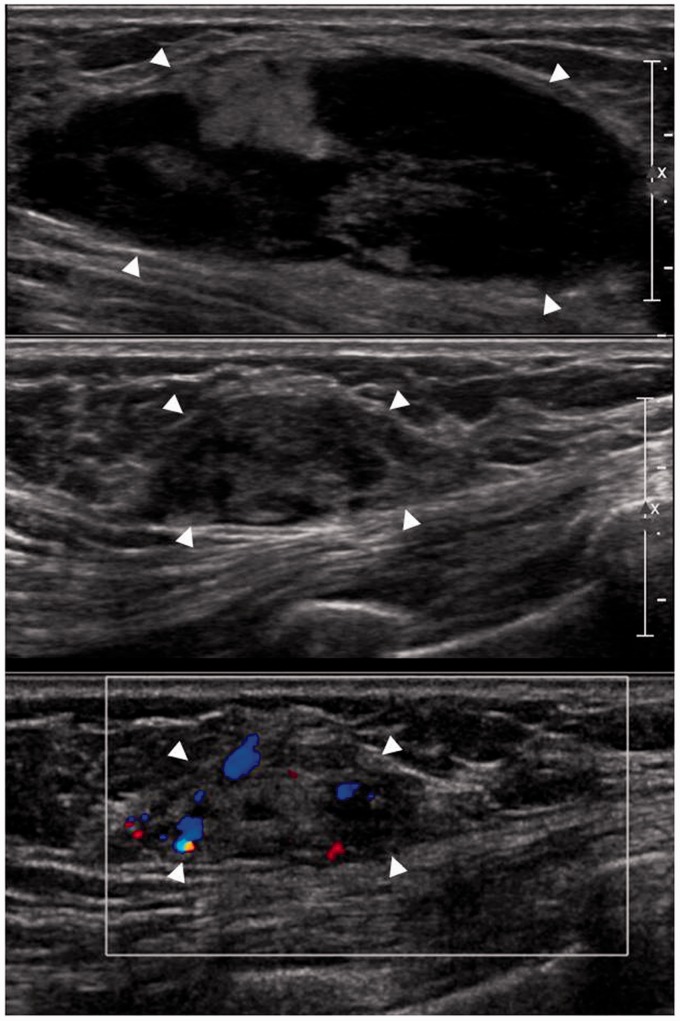

乳腺浆细胞瘤(BP)是一种极为罕见的多发性骨髓瘤(MM)的髓外表现。我们报告一例罕见病例的影像学发现,其中BP是MM的初始表现。一名53岁的女性,无相关病史,接受胸部计算机断层扫描以评估间歇性夜间前路胸痛,发现双侧多发乳房肿块。超声引导下的核心穿刺活检证实为BP。

Breast plasmacytoma (BP) is an extremely rare extramedullary manifestation of multiple myeloma (MM). We report the imaging findings of an unusual case in which BP was the initial presentation of MM. A 53-year-old woman with no contributory medical history underwent chest computed tomography to evaluate intermittent nocturnal anterior chest pain, and bilateral multiple breast masses were found. Following an ultrasound-guided core needle biopsy, these lesions were confirmed to be BP.